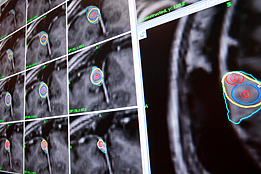

De l’immunologie, à l’imagerie en passant par la génétique, la neuro-rééducation ou encore la mémoire, le centre couvre tout un spectre de recherches tant fondamentales que cliniques tournant autour du cerveau.